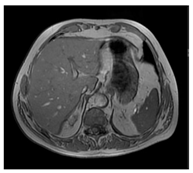

| MRI–T1 | ![]() | ![]() | ![]() |